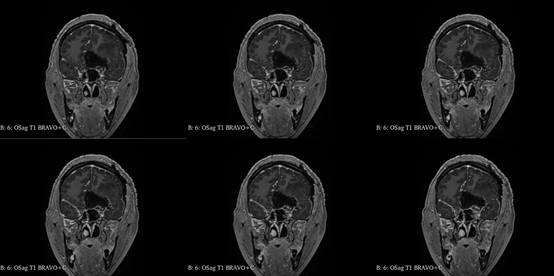

青年女性,因“左眼失明10个月,头痛3个月”就诊我院。

入院查体:神志清,精神可,言语流利,左侧瞳孔4mm>右侧瞳孔3.5mm,右侧对光反射存在,间接对光反射消失,左侧直接对光反射消失,间接对光反射存在,左眼失明,右侧鼻唇沟浅,四肢肌力及肌张力大致正常,双侧巴氏征未引出,颈软。

入院诊断:颅内占位病变(前颅窝底)脑膜瘤?;左眼失明;鼻炎

前颅窝底脑膜瘤常起源于前颅底筛骨筛板处的硬膜,瘤体多为双侧生长,少数为偏侧生长,女性稍多于男性。肿瘤可累及鸡冠和蝶骨平台的任何区域,是前颅窝肿瘤中最多见的一种。因为肿瘤位于前颅窝底,额叶在功能上属于“哑区”,患者就诊发现肿瘤时瘤体多已巨大。主要症状可有颅内压增高症状、视力减退、癫痫以及精神症状等。该患者主因“左眼失明10个月,头痛3个月”就诊。术中采用双额冠状开颅,左侧为主,由于肿瘤体积巨大,术中切除少许薄层额叶脑组织,边离断基底、边瘤内减压,分块切除肿瘤,最终探查肿瘤基底主要位于鸡冠、筛板、蝶骨平台、鞍结节、前床突处硬膜,术中见肿瘤供血主要来源于前颅窝底硬膜及大脑前动脉分支,术中仔细辨认供血动脉、过路血管,大脑前动脉及其分支保护完好,术中见视神经、视交叉受压明显,尤其是左侧视神经已缺血苍白,最终达Simpson II级切除。术者体会,该患者术前行多模态重建,可见瘤表数条粗大的静脉,术中切莫过早离断肿瘤的引流静脉,以防因引流不畅致瘤体肿胀出血;术前行多模态重建,利于鉴别供血动脉、过路血管,早期离断供血动脉更利于肿瘤切除;该类肿瘤基底一般较为广泛,不能盲目离断基底,尤其是近鞍结节处,可以于中线处离断基底,进入第一间隙后向两侧探查并保护视神经,待充分缩小瘤体看清楚毗邻的血管神经后再将其完全切除;术毕做好多层颅底重建以防脑脊液漏。另外,该患者术前左眼失明已达10个月,术后第1天即有光感,术后1月复查左眼视力可达50cm内数指,这在临床中非常少见,对于此类病人,不要轻易放弃挽救视力的任何机会。